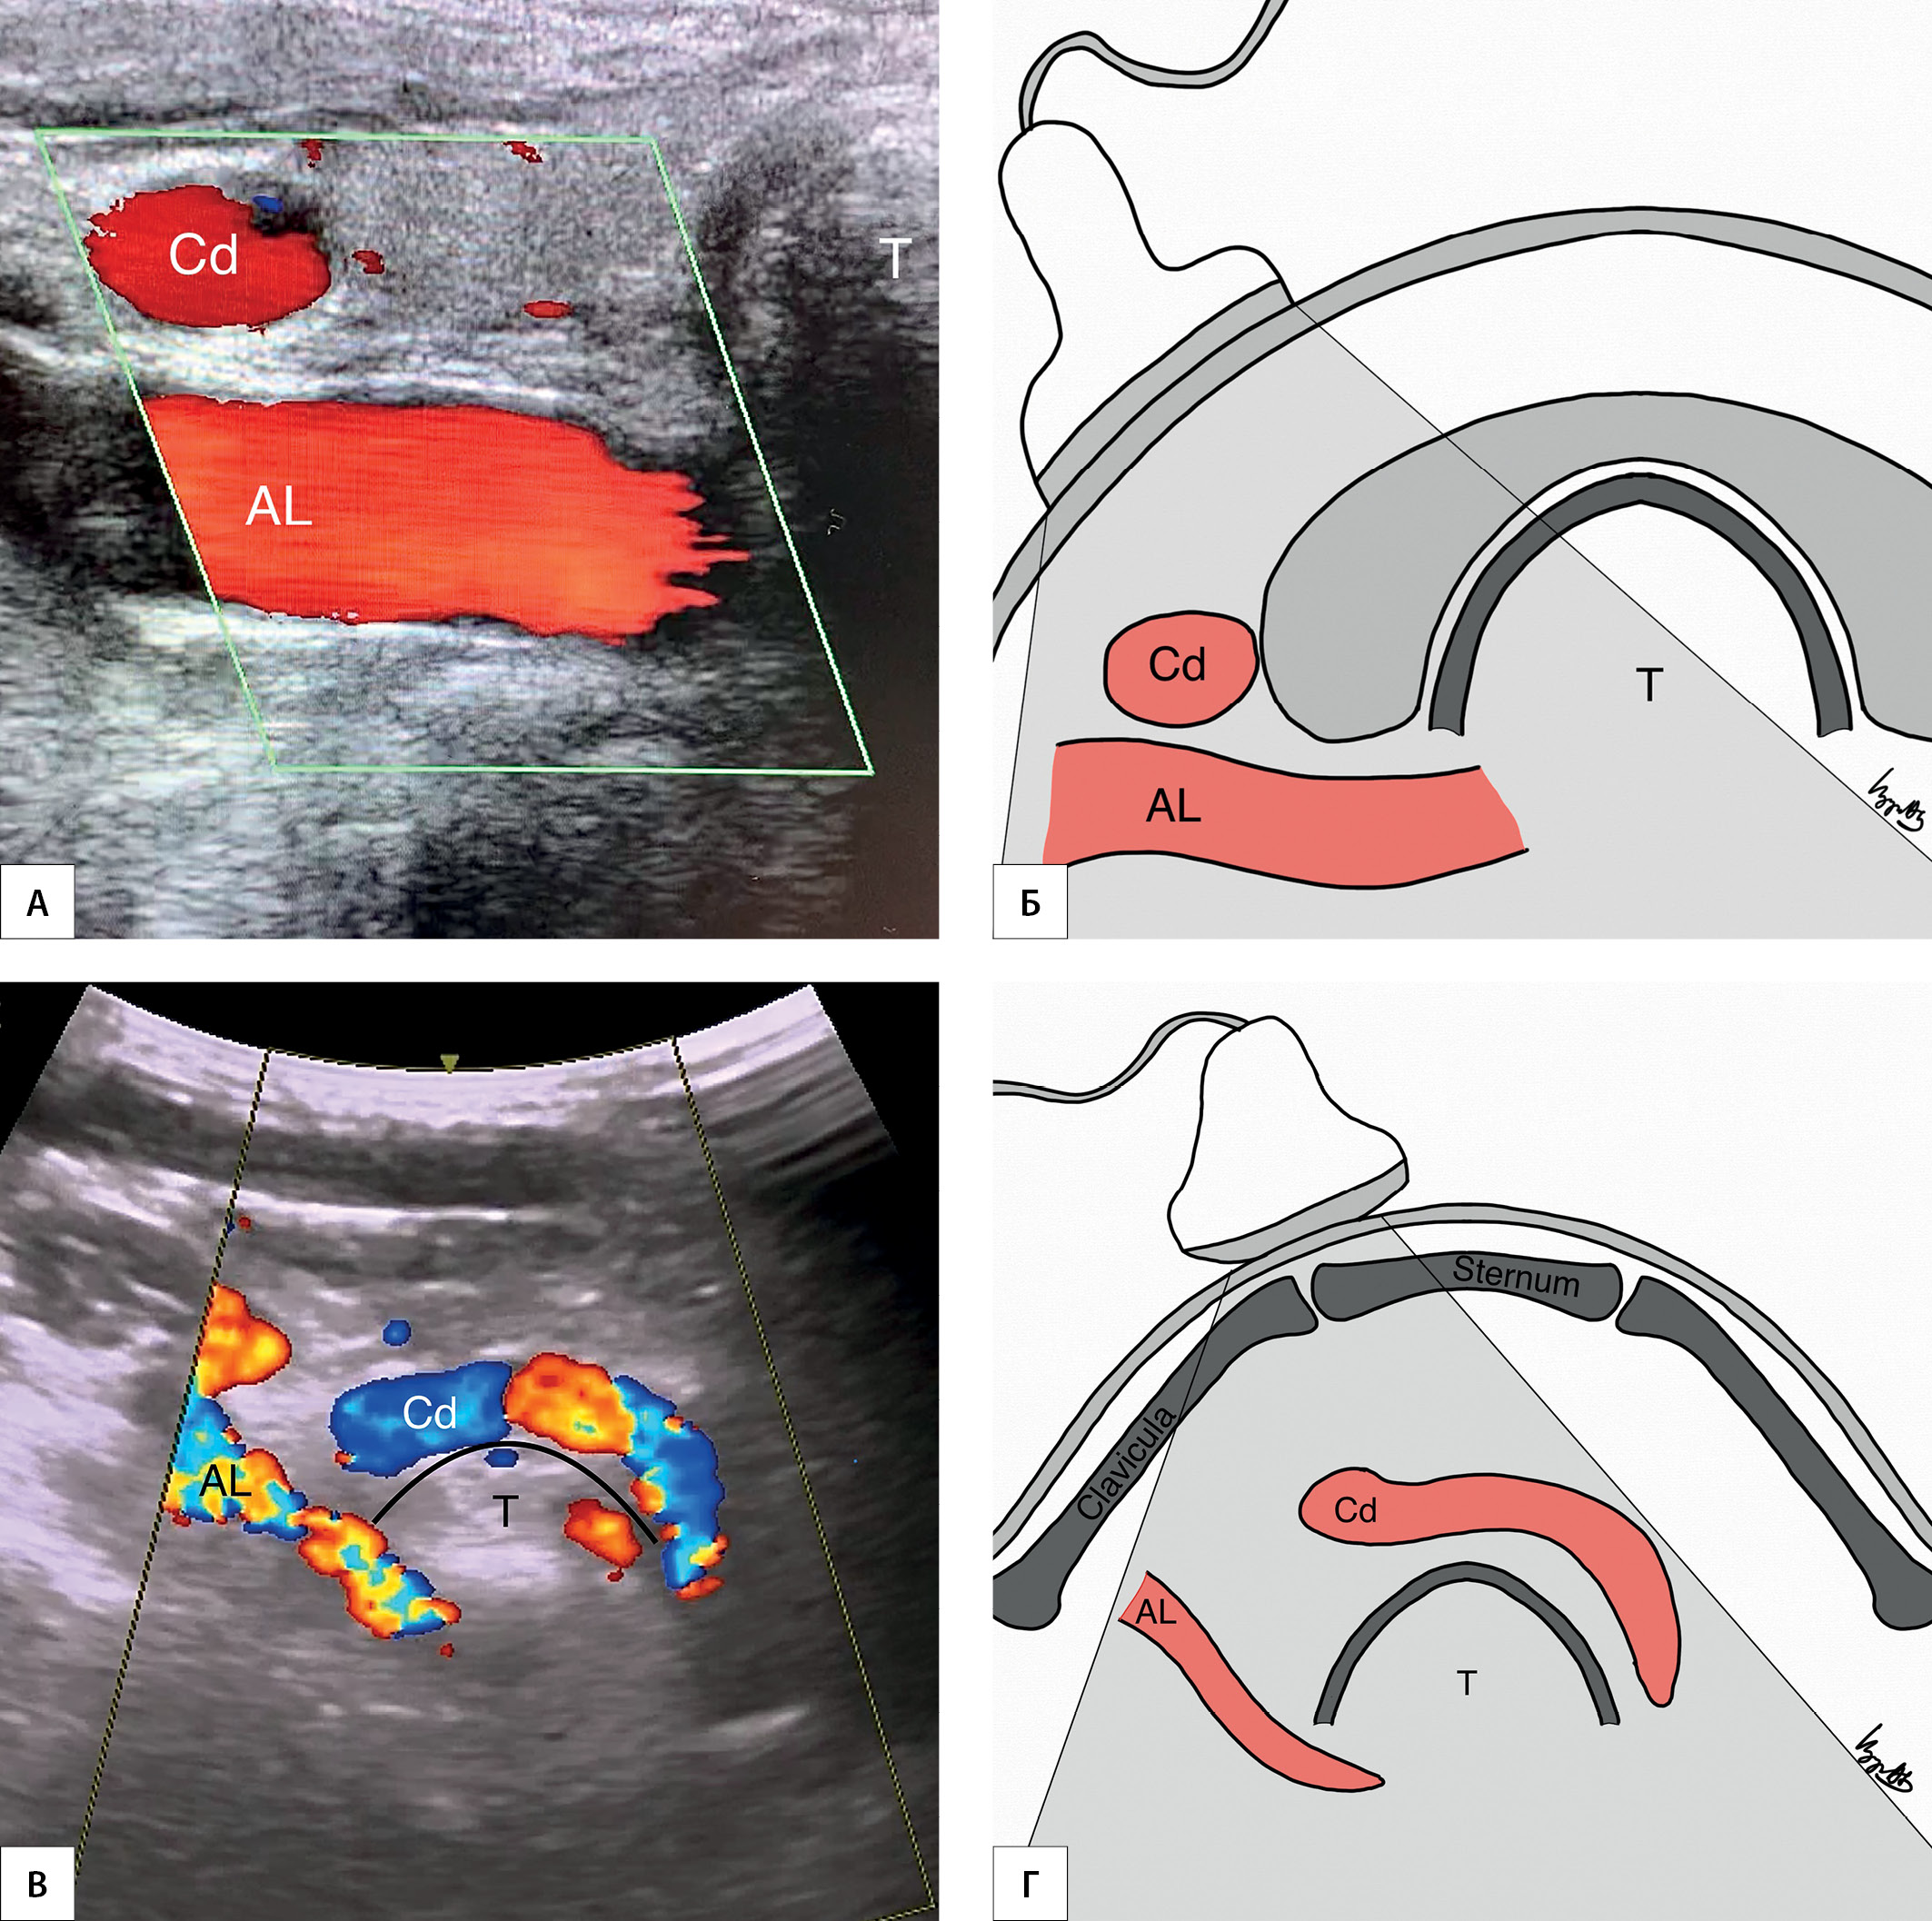

МАТЕРИАЛЫ И МЕТОДЫ. В исследование включены пациенты, которым выполнялись операции на щитовидной или околощитовидных железах с выделением правого нижнего гортанного нерва. В предоперационном периоде проводились УЗИ сосудов шеи с визуализацией брахиоцефального ствола (Y-признака) и правой аберрантной подключичной артерии (AL-признак). При интраоперационном выявлении невозвратного гортанного нерва в послеоперационном периоде проводилась компьютерная томография сосудов шеи.

РЕЗУЛЬТАТЫ. В исследование включены 1476 пациентов. Y-признак отмечен у 1338 (90,7%) пациентов. У данного контингента больных определялась типичная анатомия возвратного гортанного нерва. В 138 (9,3%) случаях Y-признак выявить не удалось. В этой подгруппе в 20 (1,4%) наблюдениях отмечены невозвратный гортанный нерв и правая аберрантная подключичная артерия. Таким образом, чувствительность Y-признака в диагностике нормальной анатомии возвратного гортанного нерва составила 100%, специфичность — 91,9%, положительная прогностическая ценность — 14,5%, отрицательная прогностическая ценность — 100%. Напротив, AL-признак отмечен у всех пациентов с невозвратным гортанным нервом и правой аберрантной подключичной артерией. Ложноположительных и ложноотрицательных результатов не отмечено. На основе анализа интраоперационных картин выделено три варианта невозвратного гортанного нерва: I тип (верхний) — расположен позади верхней трети доли щитовидной железы, имеет прямое нисходящее направление и образует угол к гортани в 30–50°; III тип (нижний) — имеет прямое восходящее направление (имитирует ход возвратного гортанного нерва) и образует угол к трахее в 30–50°; II тип (средний) — все варианты невозвратного гортанного нерва, расположенного между I и III типами.

ЗАКЛЮЧЕНИЕ. Выявление брахиоцефального ствола (Y-признака) при УЗИ подтверждает наличие у пациента возвратного гортанного нерва (чувствительность 100%), а визуализация правой аберрантной подключичной артерии (AL-признака) определяет наличие невозвратного гортанного нерва (чувствительность и специфичность 100%).

2. Рисунок 2. Эхографические признаки AL (AL-признак). | |